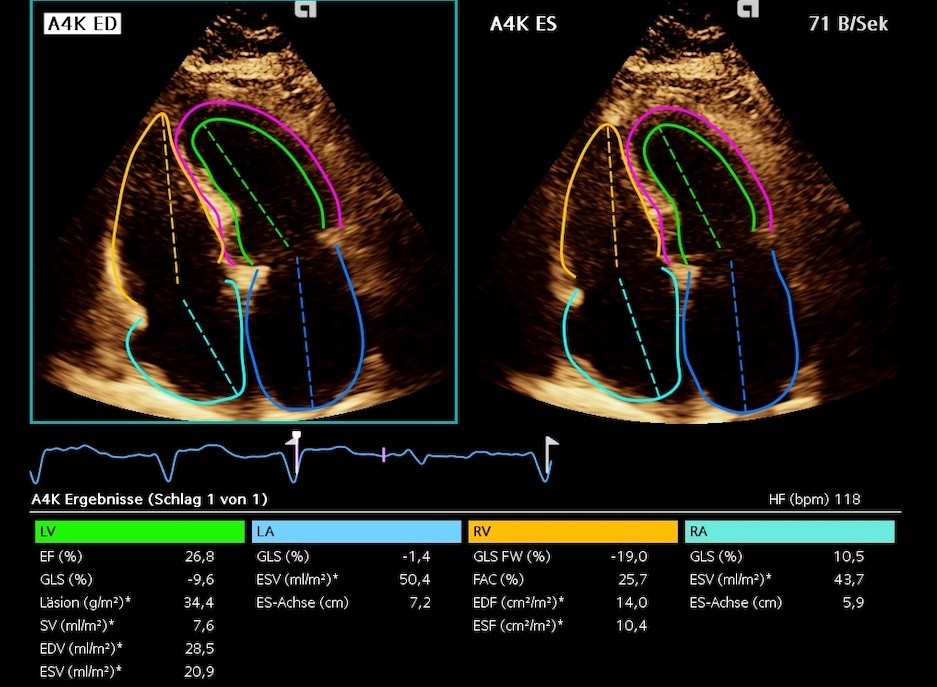

RA strain & HFrEF

Severely reduced RASr — elevated RA & RV filling pressures

LA strain & HFrEF

Severely reduced LASr (3% & 5,9%) in HFrEF

GLS severely reduced (-3,9%), moderately reduced -12,2% (HFimpEF), mildly reduced -14,6% (HFpEF)